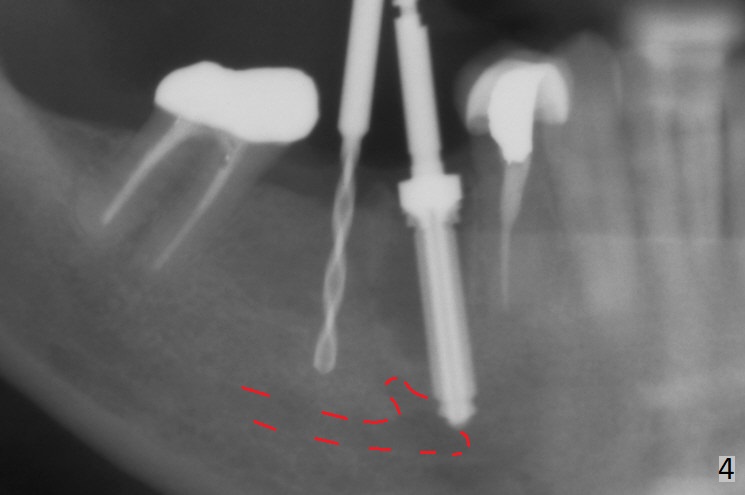

Preop examination shows that the buccal plate at #30 is atrophic (Fig.1 *). The mesiodistal width of the pontic is narrow as compared to the retainer at #31 (Fig.2). It appears that a narrow implant should be placed at #30 and should be able to sustain functional loading. After ridge reduction at #30 (Fig.3 ^) and extraction and debridement at #29, osteotomies at these sites are initiated with 1.2 mm and 2 mm drills, respectively. Probably due to low bone density, the osteotomy at #29 drops deep and close the Mental Loop (red dashed line). While the trajectory at #30 improves, the osteotomy at #29 remains close to the Mental Loop (Fig.4), asymptomatic with infiltration anesthesia. A 3x12(2) mm 1-piece implant is placed at #30 and 3.8x16 mm 2-piece implant at #29 (Fig.5,6 with insertion torque >50 and <50 Ncm, respectively). The large distal defect at #29 (Fig.3,5 *, most likely due to post-related perforation) is later filled with bone graft (data not shown). After placing an abutment at #29 and suturing, periodontal dressing is applied. Three months later, the meisal gap of #29 disappears while the distal one reduces (Fig.7 *). The abutment is changed to 4.5x4(4) mm one before reprep for impression. There is no bone loss 9 months post cementation (Fig.8) or 3 years 9 months post cementation (Fig.9). In fact the crown is lost at #31. At repeated request from the patient, a prefabricated post and crown will be fabricated for short term purpose while an implant is going to be placed at #19. The new crown at #31 has no occlusal contact (Fig.10), which may change over time.